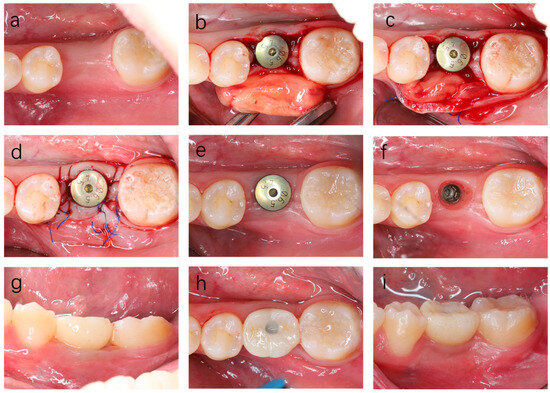

Horizontal Platelet-Rich Fibrin Membrane Block for Peri-Implant Soft Tissue Augmentation: An Experimental Animal Study with Clinical Illustration

Background/Objectives: Adequate peri-implant soft tissue thickness is essential for long-term peri-implant health and esthetics. Horizontal platelet-rich fibrin (H-PRF) has been proposed to support soft tissue regeneration; however, experimental and translational evidence for its application in peri-implant soft tissue augmentation remains limited. This study [...] Read more.

Background/Objectives: Adequate peri-implant soft tissue thickness is essential for long-term peri-implant health and esthetics. Horizontal platelet-rich fibrin (H-PRF) has been proposed to support soft tissue regeneration; however, experimental and translational evidence for its application in peri-implant soft tissue augmentation remains limited. This study aimed to evaluate a H-PRF membrane block approach primarily through an experimental animal model, with clinical cases presented to illustrate translational feasibility. Methods: A customized compression device was used to fabricate the H-PRF membrane block. The biological performance of the H-PRF membrane block was first evaluated in a rabbit model, with histologic assessment of peri-implant soft tissue thickness and integration at 8 weeks. Representative clinical cases requiring peri-implant mucosal thickening were subsequently treated with H-PRF membrane block on the buccal aspect of the alveolar bone beneath a supra-periosteal flap to demonstrate clinical applicability. Results: In the animal model, the H-PRF membrane block resulted in a significant increase in peri-implant soft tissue thickness by increasing the lamina propria compared with control sites demonstrated by histologic analysis. The clinical illustrations showed stable buccal soft tissue volume and contour with minimal patient morbidity. Conclusions: Within the limitations of this experimental study, the horizontal H-PRF membrane block technique demonstrated promising biological performance for peri-implant soft tissue augmentation in an animal model. The accompanying clinical illustrations support the translational feasibility of this approach. Clinical relevance: This experimental study provides biological and translational insight into a minimally invasive strategy for peri-implant soft tissue thickening and may inform future controlled clinical investigations. Full article